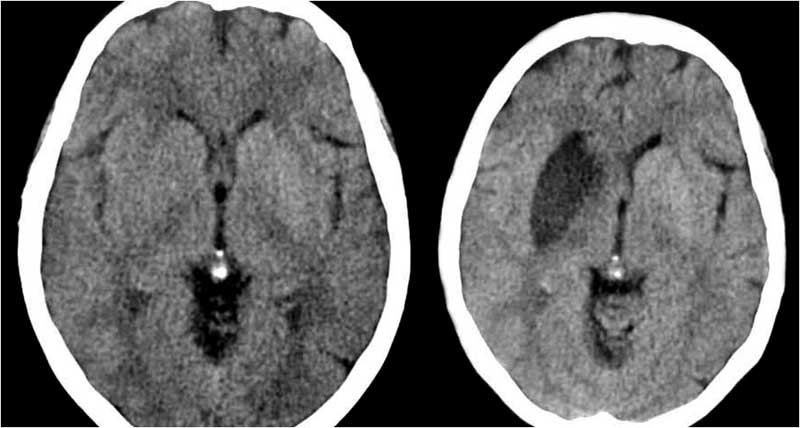

SIGNO DE LA ARTERIA BASILAR HIPERDENSA

Es un signo precoz de infarto por obstrucción por trombo o émbolo de la arteria basilar. El significado de la imagen es el mismo que el de la arteria cerebral media hiperdensa. Sin embargo es un hallazgo mucho menos común, menos reconocible, y cuya sensibilidad y especificidad no se ha determinado, a diferencia del signo de la arteria cerebral media hiperdensa.

La dificultad en reconocerlo estriba en la menor resolución de la tomografía para la valoración de la fosa posterior, en el trayecto del vaso transversal al plano axial (visible en pocos cortes), en la falta de referencia contralateral, y en la menor frecuencia y conocimiento de este hallazgo. La realización de cortes finos y de reconstrucciones multiplanares puede ayudar a mejorar a identificar el signo.

El caso que presentamos muestra el signo el signo en el estudio inicial del paciente (a la izquierda) y el infarto en la protuberancia en un nuevo estudio realizado a las 12 horas.

La obstrucción de la arteria basilar puede provocar un cuadro con un pésimo pronóstico ya que la mortalidad supera el 90 % de casos.